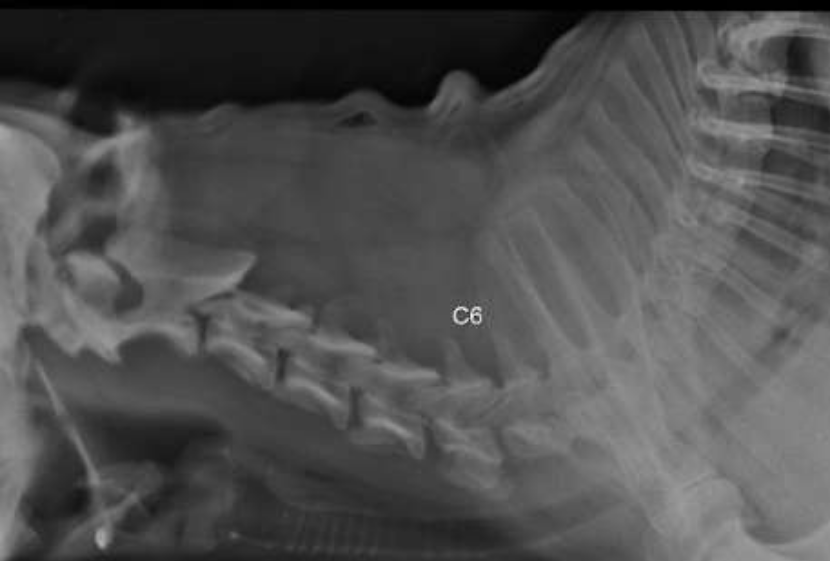

RX Transición CT conservada, en dorsal del espacio intervertebral entre C5-C6 se observa un aumento de radio densidad, mineralización incipiente de disco intervertebral?, se sospecha mismo proceso, con menor intensidad a nivel C4-C5, se sugiere control radiográfico.

Conclusion: Imágenes obtenidas de columna cervical, compatibles con afección compresiva y degenerativa discalmúltiple, con lesión de mayor relevancia a nivel C3-4, según descripción previa.